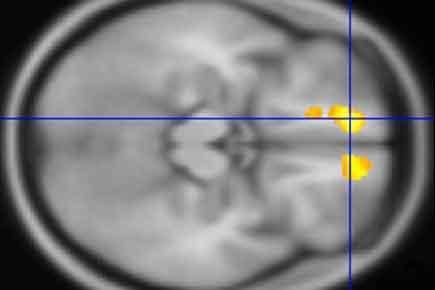

Researchers at Washington University School of Medicine in St. Louis have identified areas in the brains of children with Tourette's syndrome that appear markedly different from the same areas in brains of children who don't have the disorder. Above, in a scan of a child with Tourette's, yellow indicates an area with less white matter than in the same brain region in kids who don't have the disorder. The scans also revealed areas in the brains of kids with Tourette's that have more gray matter than in children without the condition. Credit: Washington University School of Medicine

In kids with Tourette's, the researchers also found less white matter around the orbital prefrontal cortex, just above the eyes, and in the medial prefrontal cortex, also near the front, than in kids without the condition.